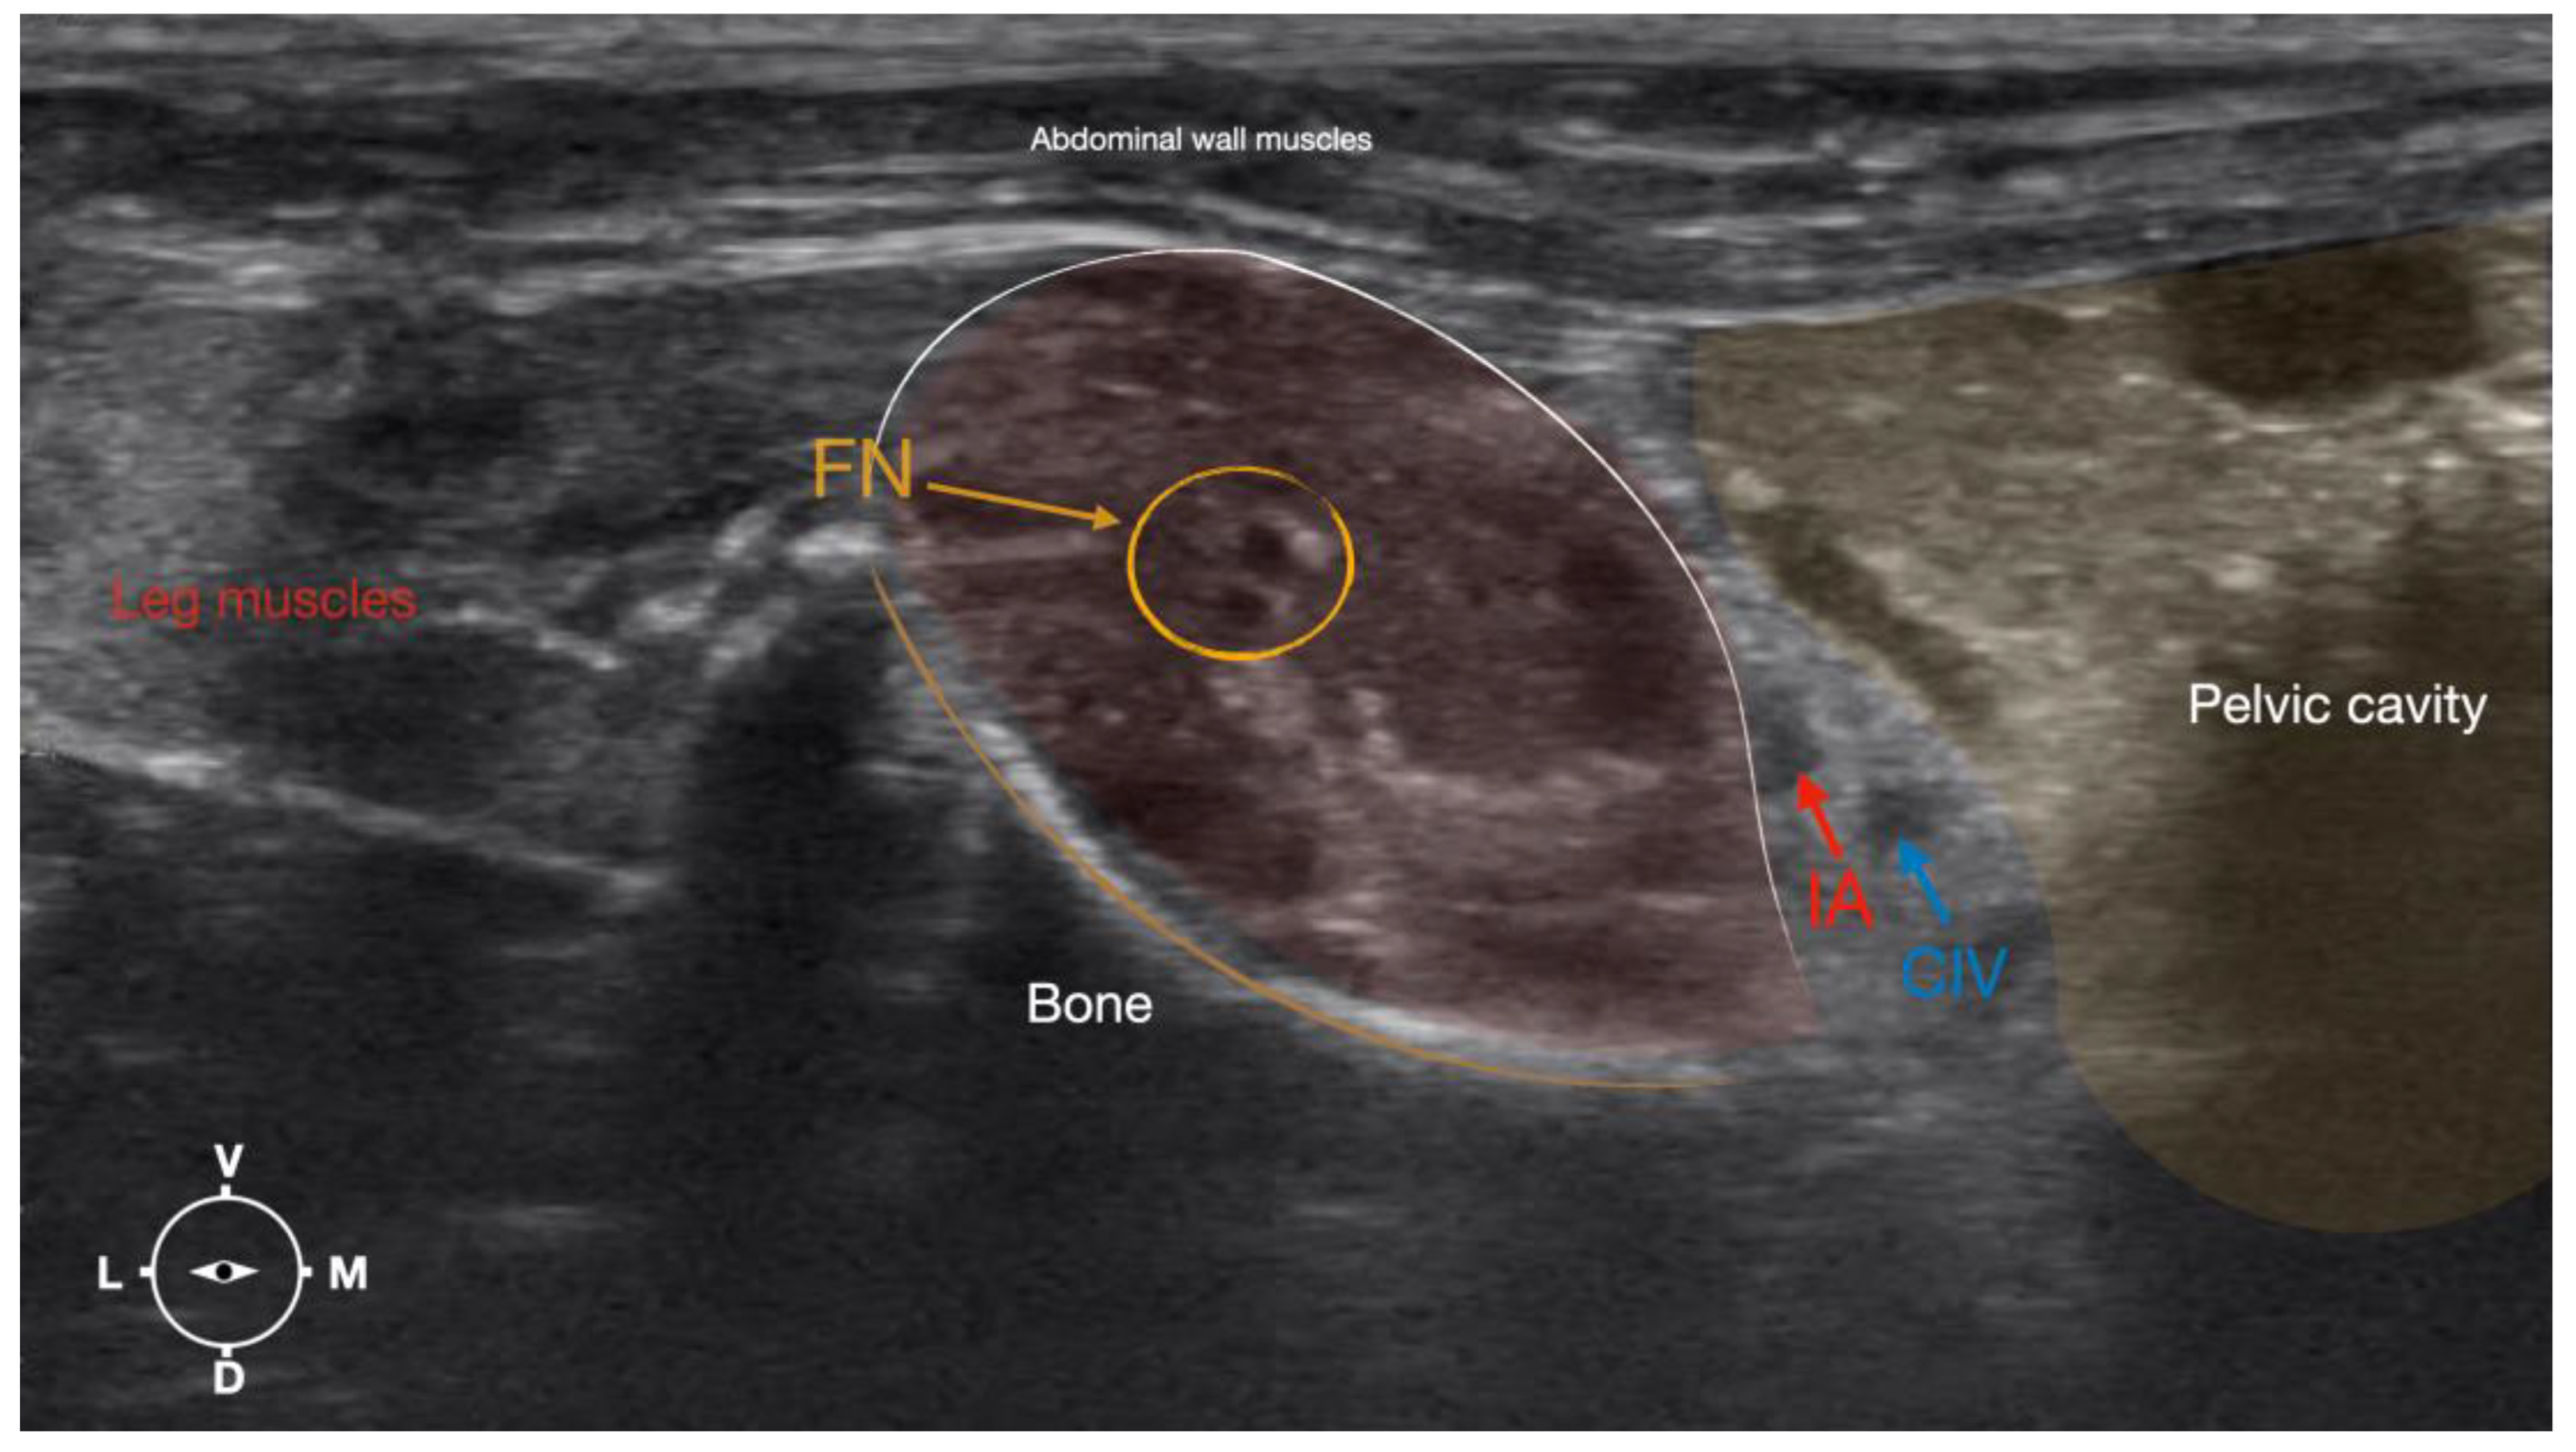

Figure 4.

Corresponding transverse ultrasound image to Figure 5. The window of interest was set at a depth of 2 cm and the focus was at the level of the femoral nerve to optimize the image quality. The ultrasound image shows the FN and related structures. IA, iliac artery, CIV, common iliac vein; FN, femoral nerve; D, dorsal; L, lateral; M, medial; V, ventral.

Based on the anatomical dissection and the US scans performed in this phase, the best way to locate and inject the FN was achieved by scanning the IPM from the projection of the iliac crest in the caudal direction. Ultrasonographically, the femoral nerve appeared as a hypoechoic structure in the dorsal part of the IPM, becoming hyperechoic/honey-comb-like in the ventral part of the mentioned muscle. The IPM was displayed as structures with heterogeneous echogenicity. The ilium and the vertebrae were displayed as a hyperechoic structure with acoustic shadow and located lateral and dorsal to the femoral nerve, respectively.